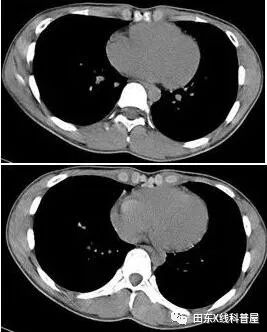

患者女,64岁,发作性心悸入院

急诊心电图:室上性心动过速,异常Q波,T波异常,右心室肥厚,心率111次/分